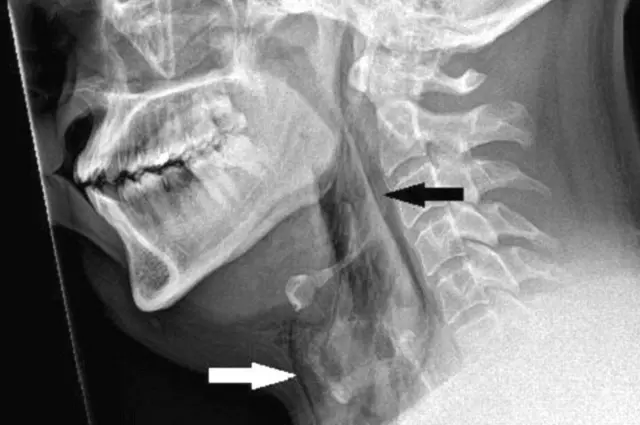

அவ்வாறு தும்மலை அடக்கியதால் அவரது மூச்சுக்குழாயில் 2 மி.மீ. வரை காயம் ஏற்பட்டிருப்பது ஸ்கேன் மூலம் தெரியவந்தது.

ஒருவர் தும்மும்போது வாய் மற்றும் மூக்கை மூடினால் மூச்சுக்குழாயின் மேல் பகுதியில் அழுத்தம் 20 மடங்கு அதிகரிக்கும் என, டண்டீ பல்கலைக்கழக மருத்துவர்கள் கூறுகின்றனர்.

தும்மலை நிறுத்துவது திடீரென மூச்சுக்குழாயில் கடுமையான காயத்தை ஏற்படுத்தும், இது மருத்துவ ரீதியாக "தன்னிச்சையான மூச்சுக்குழாய் துளையிடல்" ( "spontaneous tracheal perforation" ) என கூறப்படுகிறது. இதுபோன்ற சம்பவங்கள் அரிதாகவே காணப்படுகின்றன என்று மருத்துவர்கள் கூறினாலும், சில சமயங்களில் அது ஆபத்தானது.